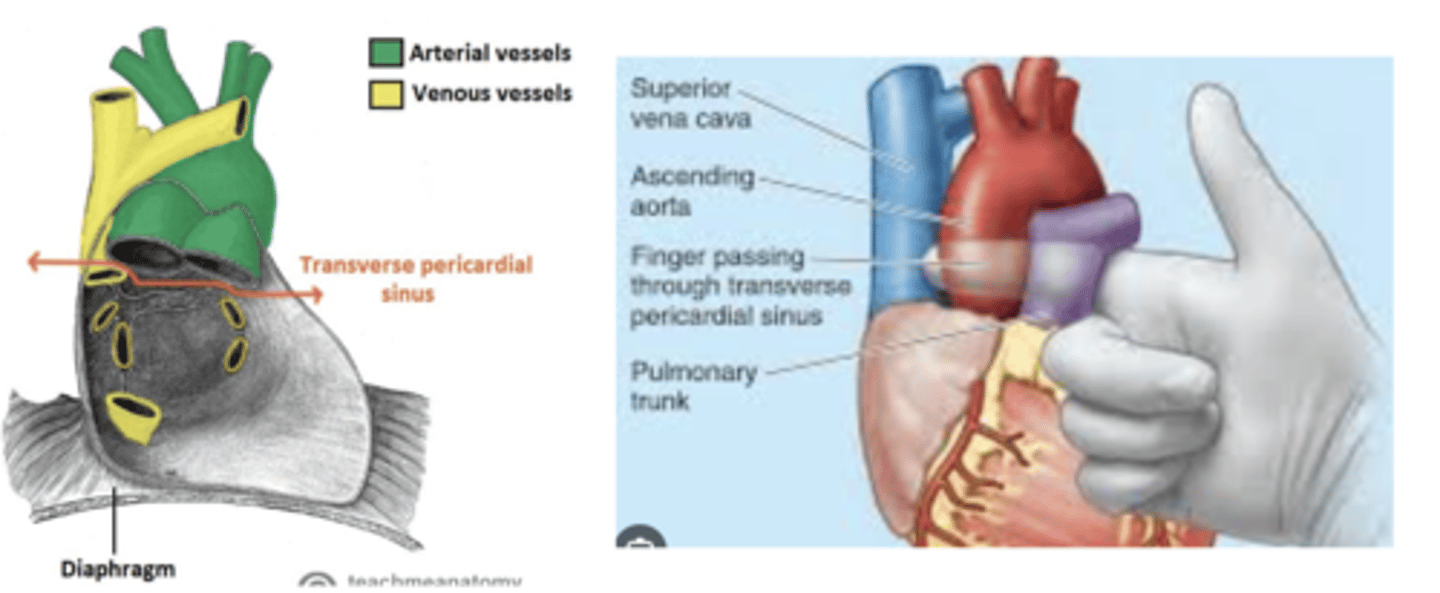

What is the transverse sinus of the pericardium ?

. space posterior to the aorta and pulmonary trunk

. anterior to vena cava

Clinical significance of the transverse sinus?

Surgeons use it during cardiac procedures.

By passing a finger or clamp through the sinus they can isolate these arteries and control blood flow to the heart during surgeries like coronary artery bypass grafting (CABG).